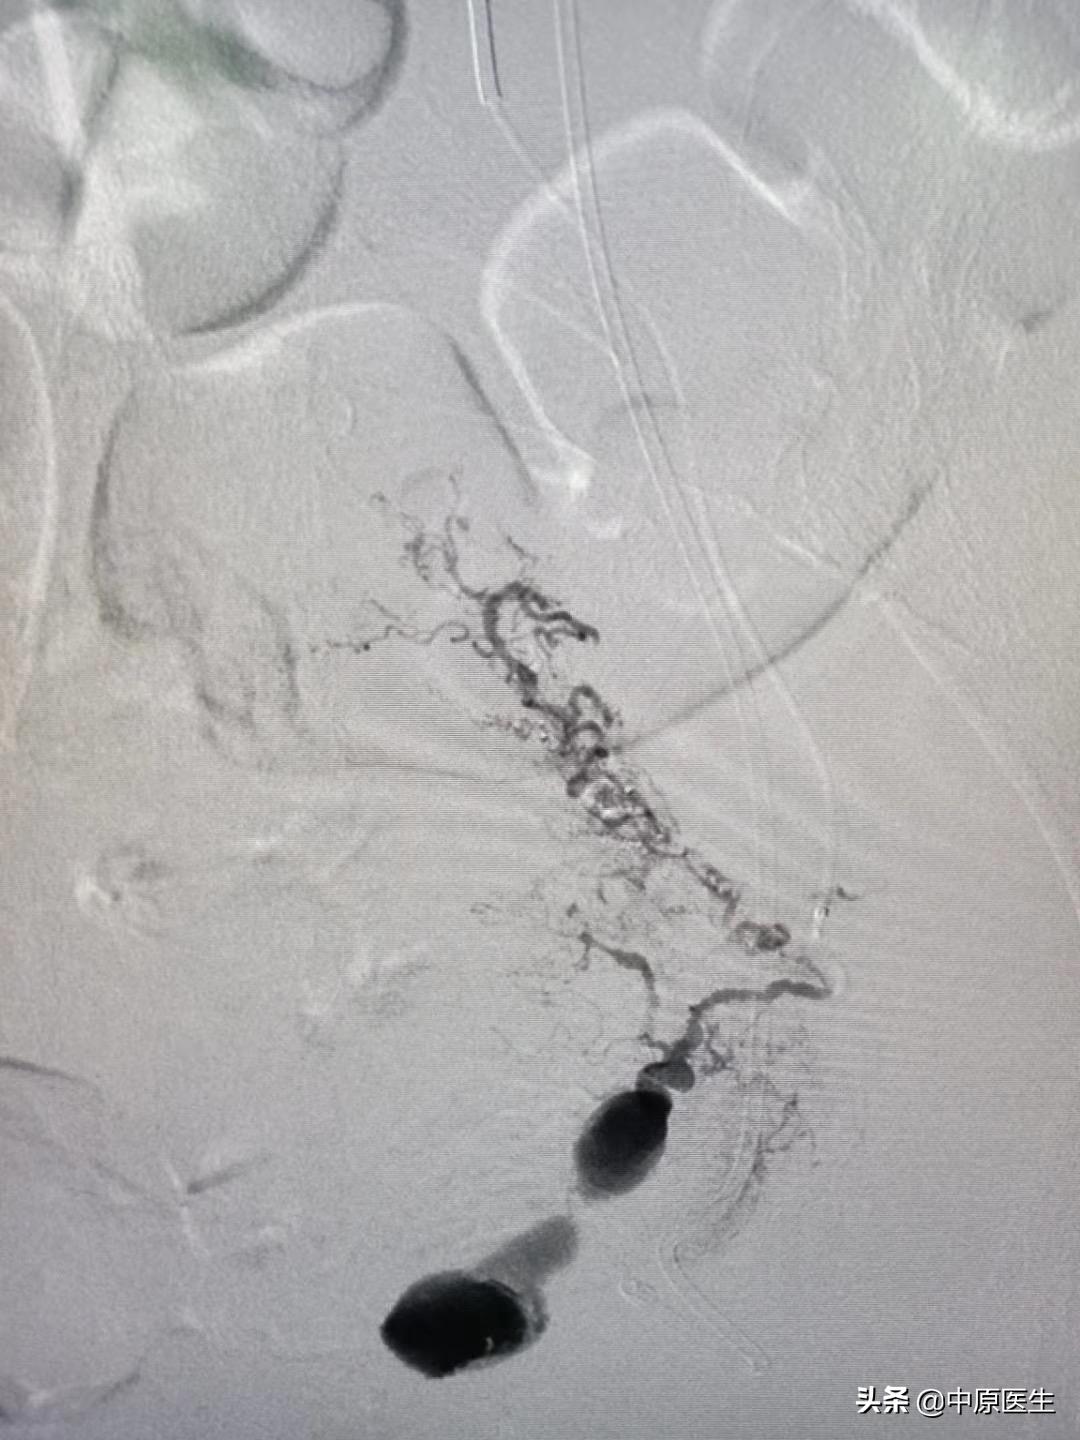

我处理好门诊事宜,十点赶往导管室,按标准预防做好术前防护、术前准备工作。在导管室的护士、技师等积极配合下,手术顺利开展,造影显示左侧子宫动脉近宫颈处有一破口、形成假性动脉瘤,假性动脉瘤破溃,造影剂快速流入宫腔内(相当于找到了河流的决口处);紧急用生物胶栓塞该破口及其远、近端血管(相当于堵住了决口及其上下游,上游流不进来、下游的倒灌不了),复查造影未见造影剂外渗、动脉瘤、静脉早显等异常血管影(成功止血)。然后选择双侧髂内动脉各分支造影未见明显异常血管,再予右侧子宫动脉栓塞。半小时顺利完成手术,病人生命体征平稳。安全送回病房,继续药物治疗。